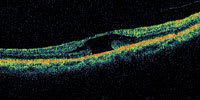

Figure 1. OCT showing early macular hole formation. The lateral separation is less than 50 μm. |

A central clinical challenge has been accurately diagnosing early macular holes which may be mimicked by many other conditions.34,35 No imaging modality has enhanced our diagnostic capability more than the OCT; superior imaging capabilities have improved diagnostic accuracy, clinical monitoring, and postoperative assessment.36-38 The OCT unequivocally demonstrates early stages of full-thickness macular holes (Figure 1), and allows distinction of pseudohole and pre-macular hole conditions in almost all instances. Fluid accumulation in early, presumed pre-macular hole stages have been corroborated by OCT observations (Figure 2). Serial images have been reported showing the progression from apparent impending macular holes to full thickness macular holes.39-42 It has depicted many other configurations that might be in the spectrum of lamellar or pre-macular hole conditions (Figure 3 and 4).